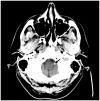

In this review article, we summarized the current advances in rescue management for reperfusion therapy of acute ischemic stroke from large vessel occlusion due to underlying intracranial atherosclerotic stenosis (ICAS). It is estimated that 24-47% of patients with acute vertebrobasilar artery occlusion have underlying ICAS and superimposed in situ thrombosis. These patients have been found to have longer procedure times, lower recanalization rates, higher rates of reocclusion and lower rates of favorable outcomes than patients with embolic occlusion. Here, we discuss the most recent literature regarding the use of glycoprotein IIb/IIIa inhibitors, angioplasty alone, or angioplasty with stenting for rescue therapy in the setting of failed recanalization or instant/imminent reocclusion during thrombectomy. We also present a case of rescue therapy post intravenous tPA and thrombectomy with intra-arterial tirofiban and balloon angioplasty followed by oral dual antiplatelet therapy in a patient with dominant vertebral artery occlusion due to ICAS. Based on the available literature data, we conclude that glycoprotein IIb/IIIa is a reasonably safe and effective rescue therapy for patients who have had a failed thrombectomy or have residual severe intracranial stenosis. Balloon angioplasty and/or stenting may be helpful as a rescue treatment for patients who have had a failed thrombectomy or are at risk of reocclusion. The effectiveness of immediate stenting for residual stenosis after successful thrombectomy is still uncertain. Rescue therapy does not appear to increase the risk of sICH. Randomized controlled trials are warranted to prove the efficacy of rescue therapy.